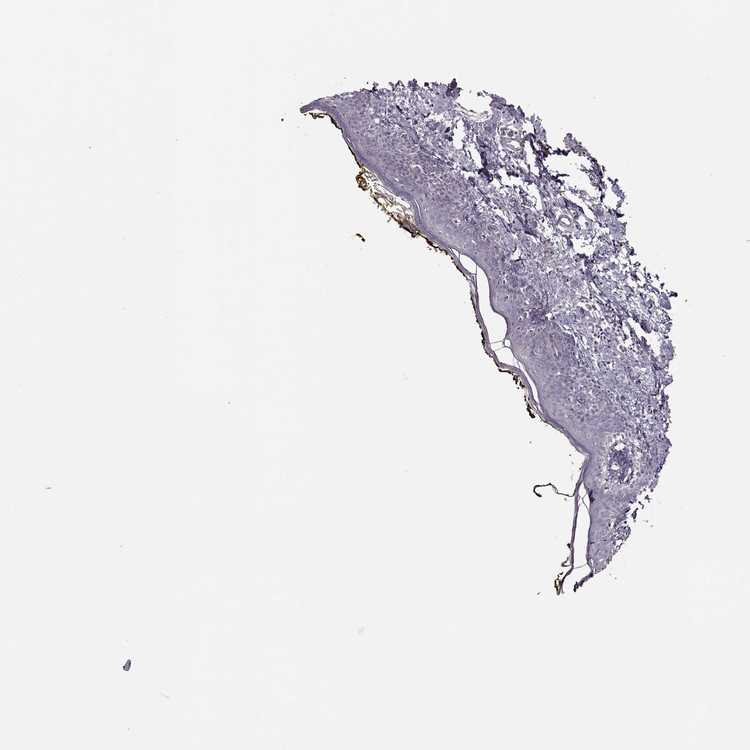

, antibody HPA007261

Epidermal cells High

SOLE OF FOOT - Extended tissue profilei

For selected proteins extended tissue profiling is performed in addition to standard tissue microarrays. The section below contains results from the extended profiling.

, antibody CAB037322